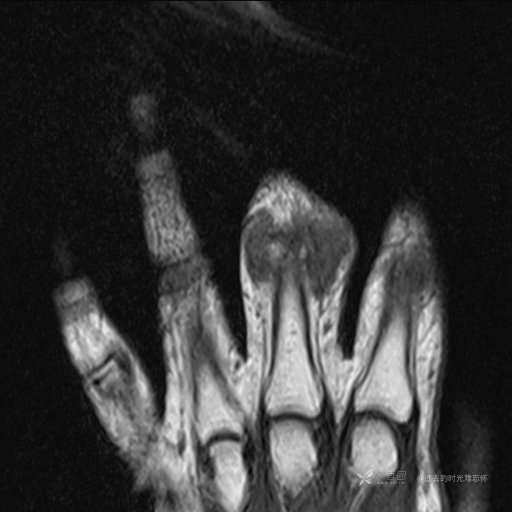

主诉: 手指肿胀2年,其间明显肿胀,抗炎后肿胀减轻,近几日肿胀疼痛加重。

T1

提示:小指是伪影。